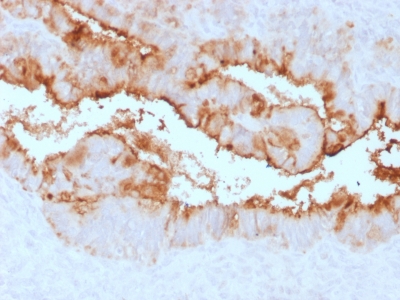

IHC (Immunohiostchemistry)

(Formalin-fixed, paraffin-embedded human Endometrial Carcinoma stained with MUC16 Rabbit Recombinant Monoclonal Antibody (OCA125/2349R).)